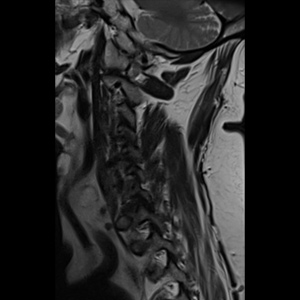

Spinal stenosis (Lumbar) Spinal stenosis (Cervical) Spinal stenosis (Thoracic) Lumbar Disc Herniation Spondylolisthesis Cervical Foraminal Stenosis Vertebroplasty Lumbar Fusion Anterior Cervical Fusion (ACDF) Posterior Cervical Fusion Thoracic Fusion Revision Lumbar Fusion Surgery Facet Joint Cyst Spinal Tumour Minimally Invasive Lumbar Fusion (XLIF) Minimally Invasive Lumbar Fusion (ALIF) Lumbar Fusion (TLIF) Thoraco-lumbar Fusion Lumbar Corpectomy Complex Lumbar Spine Surgery (Spino-pelvic fixation) Complex Cervical Spine Surgery Complex Thoracic Spine Surgery Occipito-cervical Fusion Minimally invasive surgery for thoracic disc herniation Other Related Topics